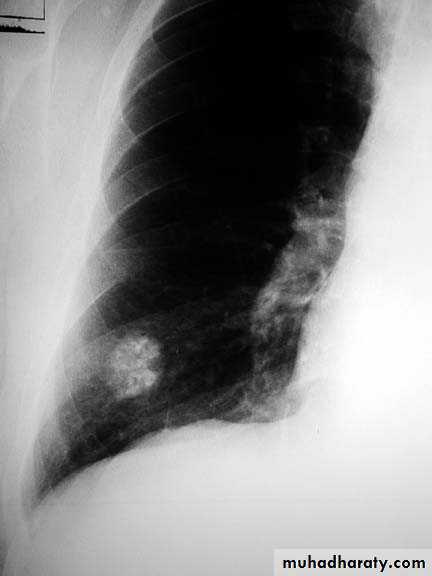

Pulmonary nodule /s1) Bronchogenic CA ( spiculated )

2)Metastasis ( multiple & different size & distribution )

3) Tuberculoma

4) hamartoma

Both are : solitary , peripheral & contain calcification )

5)Hydatid cysts

6)AVM (arterio-venous malformations which show feeding vessels